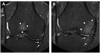

Objectives: To describe the natural history of subchondral bone marrow lesions (BMLs) in a sample of subjects with knee osteoarthritis (OA) or at risk of developing it. Additionally, to examine the association of change in BMLs from baseline to 30-month follow-up with the risk of cartilage loss in the same subregion at follow-up.

Methods: 1.0 T MRI was performed using proton density-weighted, fat-suppressed sequences. BML size and cartilage status were scored in the same subregions according to the WORMS system. Subregions were categorised based on comparison of baseline and follow-up BML status. A logistic regression model was used to assess the association of change in BML status with cartilage loss over 30 months using stable BMLs as the reference group.

Results: 395 knees were included. 66% of prevalent BMLs changed in size; 50% showed either regression or resolution at follow-up. The adjusted odds ratios (95% confidence intervals) of cartilage loss in the same subregion at follow-up for the different groups were 1.2 (0.5 to 1.6) for regressing BMLs, 0.9 (0.5 to 1.6) for resolving BMLs, 2.8 (1.5 to 5.2) for progressing BMLs, 0.2 (0.1 to 0.3) for subregions with no BMLs at baseline and follow-up and 3.5 (2.1 to 5.9) for newly developing BMLs. BML size at baseline was associated with risk of subsequent cartilage loss.

Conclusions: The majority of pre-existing BMLs decreased in size at follow-up. Absence of BMLs was associated with a decreased risk of cartilage loss, while progressing and new BMLs showed a high risk of cartilage loss in the same subregion.